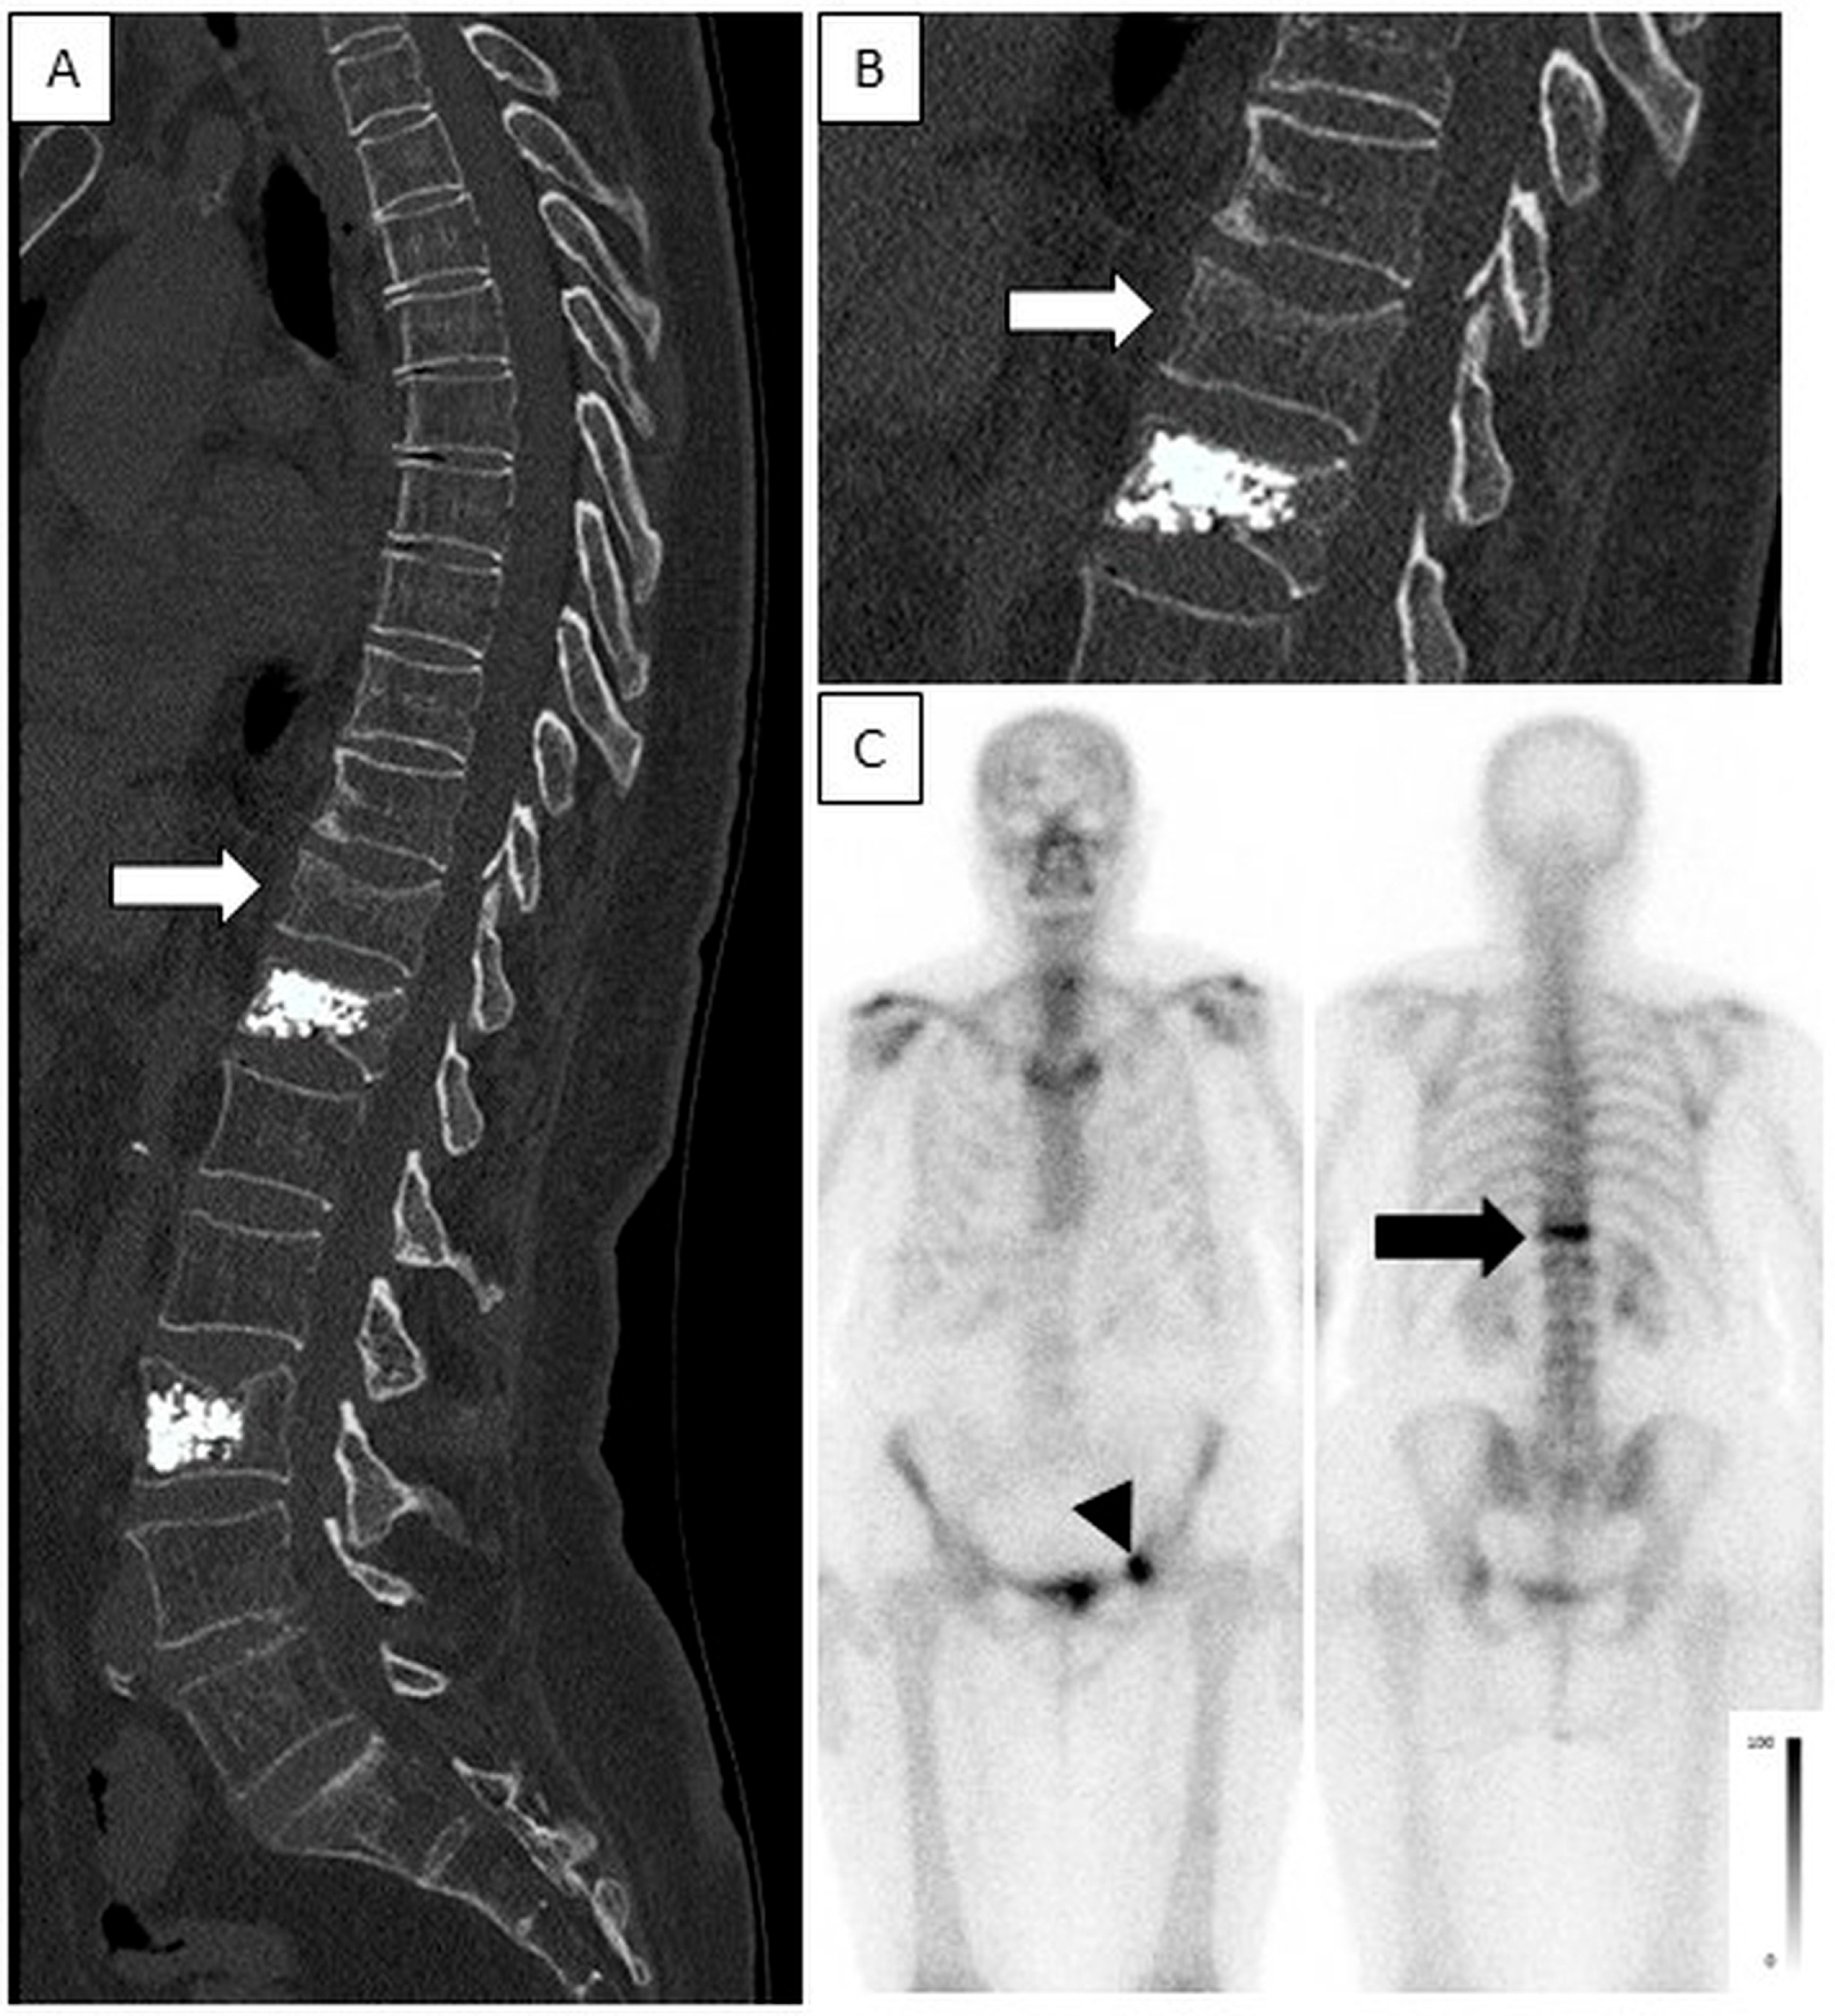

Figure 6. High-intensity uptake in an acute fracture, no uptake in chronic fractures post-vertebroplasty. A 77-year-old female after trauma. CT was acquired on the day of injury and bone scintigraphy was performed 3 days after the injury. (A,B)—Sagittal spine CT (enlarged in B) show an acute fracture in T11 (white arrow) and chronic fractures after vertebroplasty in T12 and L3. (C)—Planar anterior and posterior bone scintigraphy show high-intensity uptake in T11 (black arrow), indicating an acute fracture and no increased uptake in T12 and L3, consistent with chronic fractures. Note also, high-intensity uptake is seen in the anterior aspect of the left acetabulum (black arrow head), consistent with an acute fracture.